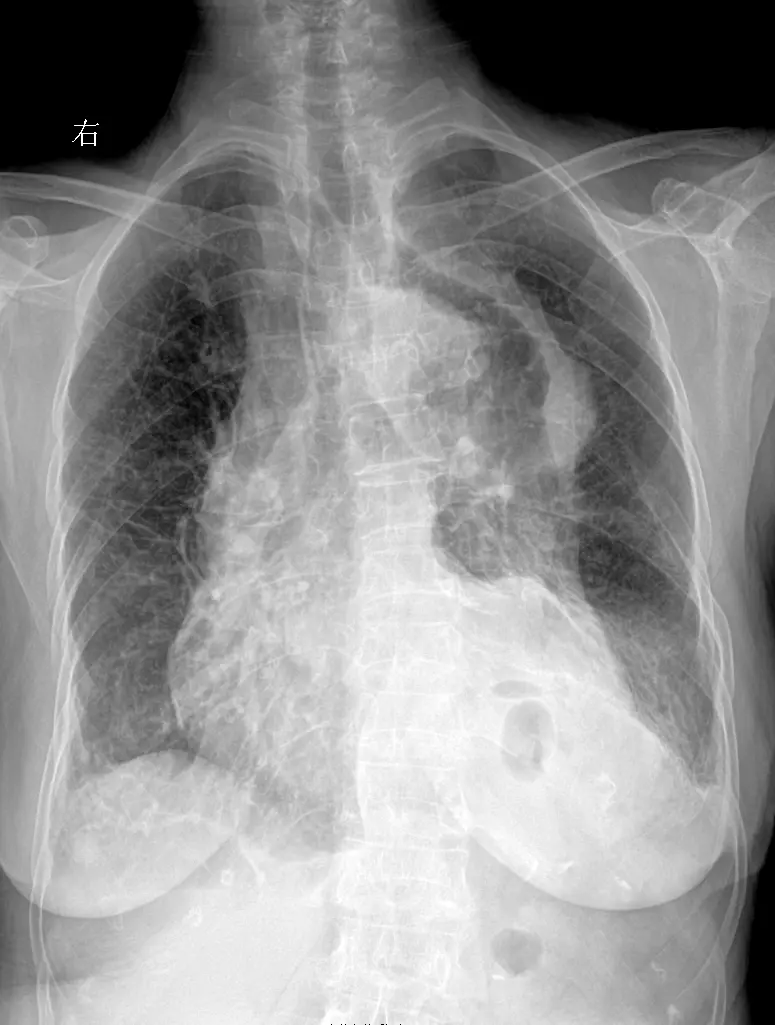

上期被查封 重新发一下家人们 再来一起探讨下肺结核 胸部正位片